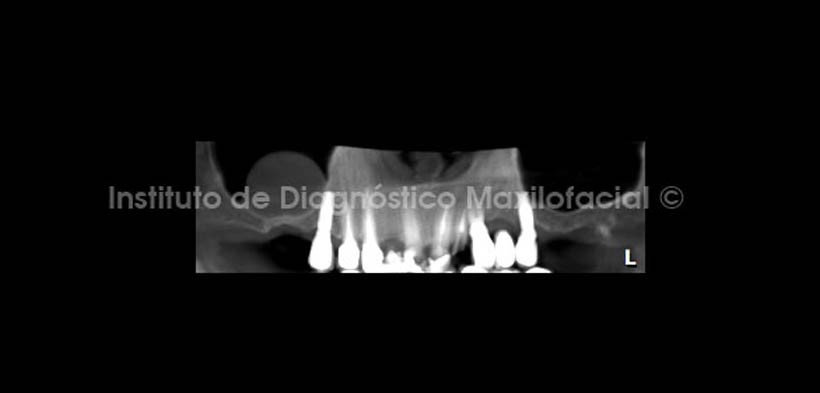

A la evaluación de la radiografía panorámica se observa una imagen de radiodensidad de tejidos blandos, de límites definidos y forma cupular, proyectada sobre el seno maxilar del lado derecho. Signos radiográficos compatibles con Quiste Mucoso de Retención (Fig. 1).